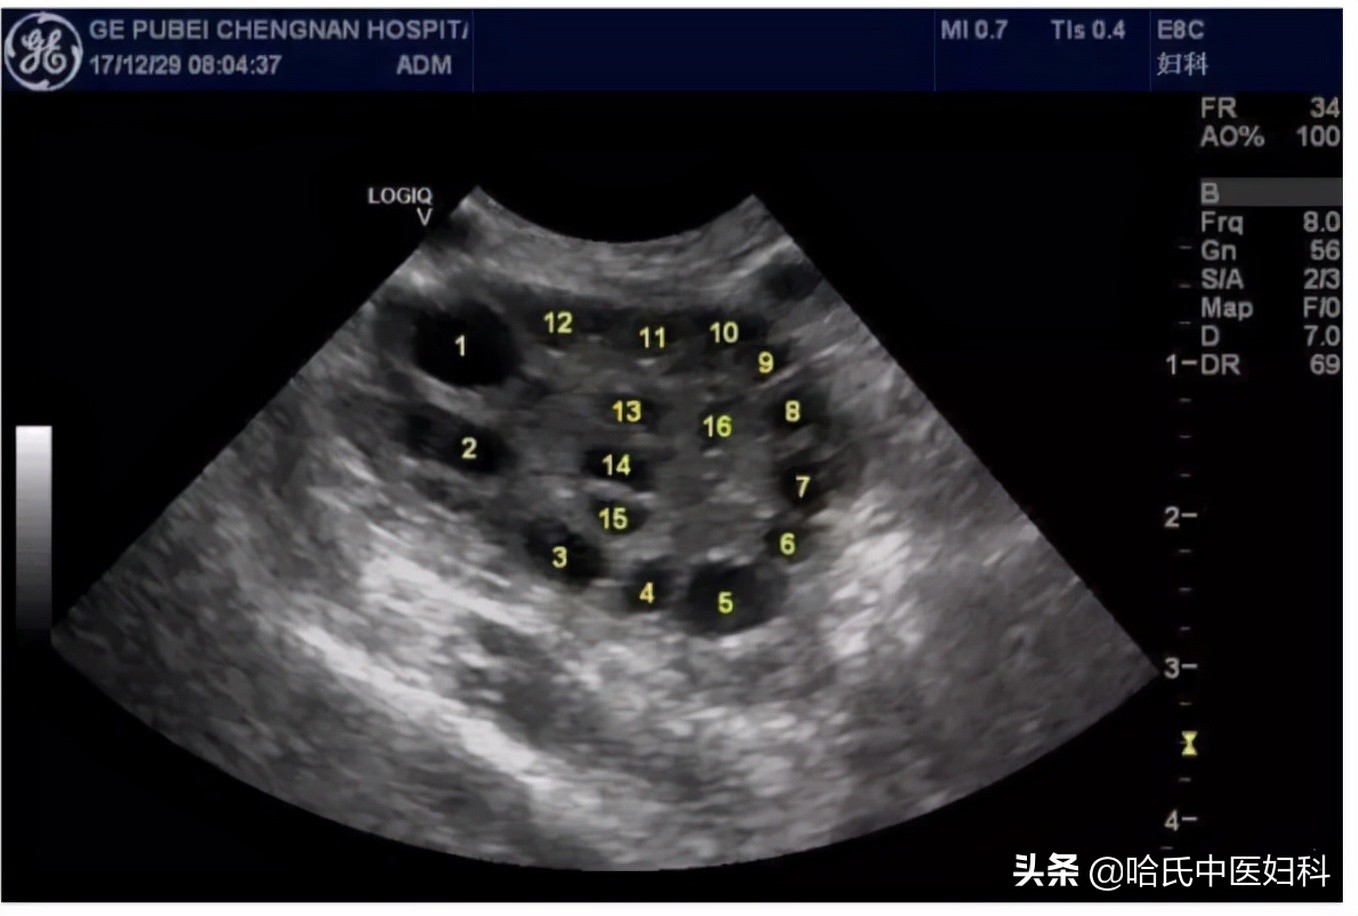

在排卵前卵泡处于生长期,由小变大,逐渐发展,如果按28天周期算,月经周期10天左右出现优势卵泡在12mm左右,然后以每天1.5-2.5mm的速度发展。

B超监测可以准确地看到卵泡的大小、发育情况并且预判排卵时间。一般于月经的第12天左右来院监测,根据卵泡发育情况医生会告知下次复查时间, 当卵泡大小在18-22mm则为成熟卵泡 ,排卵也就接近了,在视察到成熟卵泡后,建议再复查B超来视察卵泡是否已经排出。